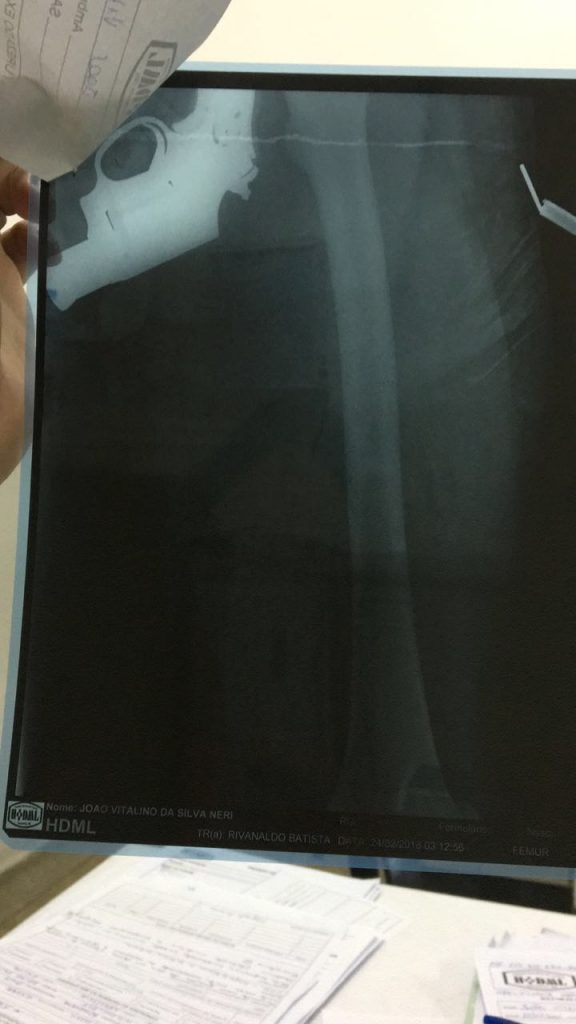

Exame de raio-x flagra homem com revólver na cintura em hospital de Parnamirim

Ao atenderem um paciente que precisou ser encaminhado para um exame de raio-x, a equipe constatou na sequência um revólver na cintura.